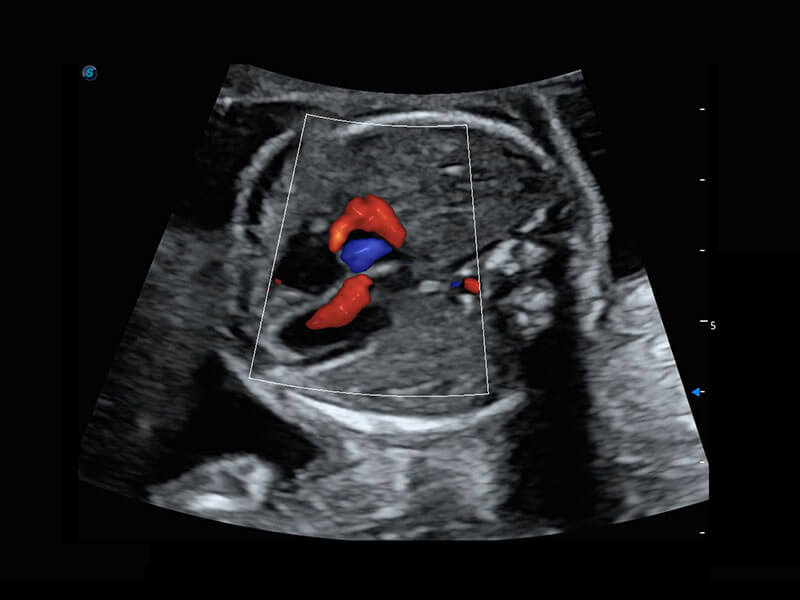

P60搭載一系列胎兒心臟成像技術(shù),實現(xiàn)精細的胎兒心臟評估。

右室雙出口

胎心容積成像